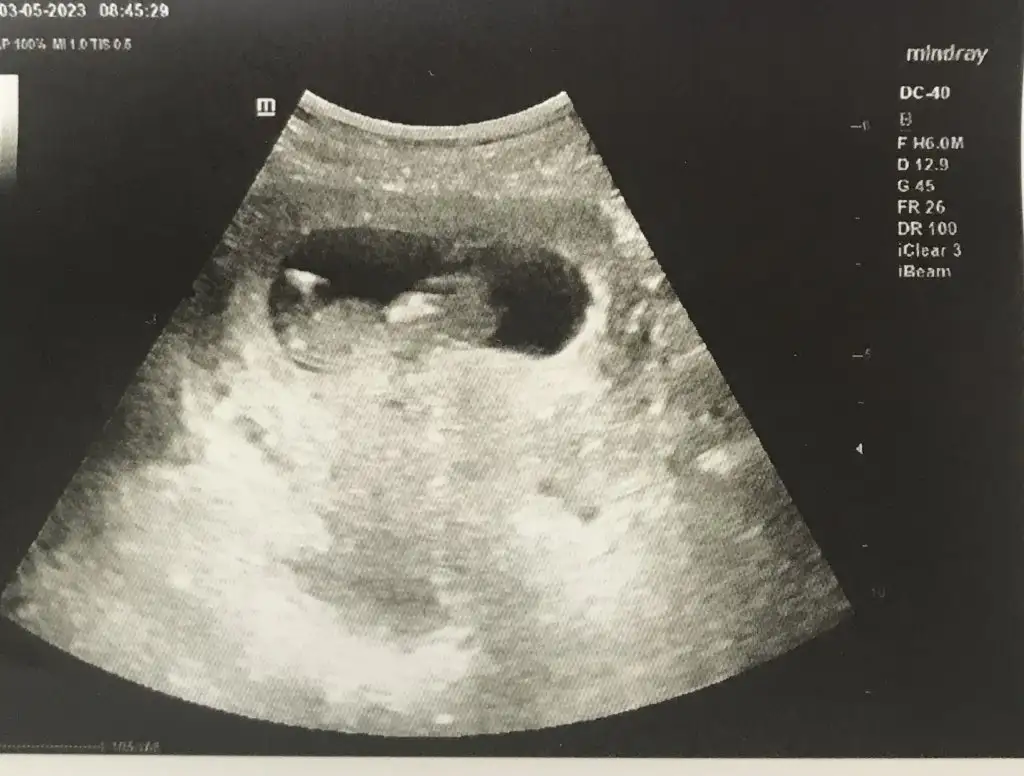

İyidirAl benden de o kadar canım çok etkileniyorum bende bugün muayene günüm heyecanla bekliyorum umarım iyi ve sağlıklıdır

İnşallah canımİyidirBugün baya kişinin kontrolü var. Buralar şenlensin, fotolarla dolsun, herkes çook güzel haberler versin umarım